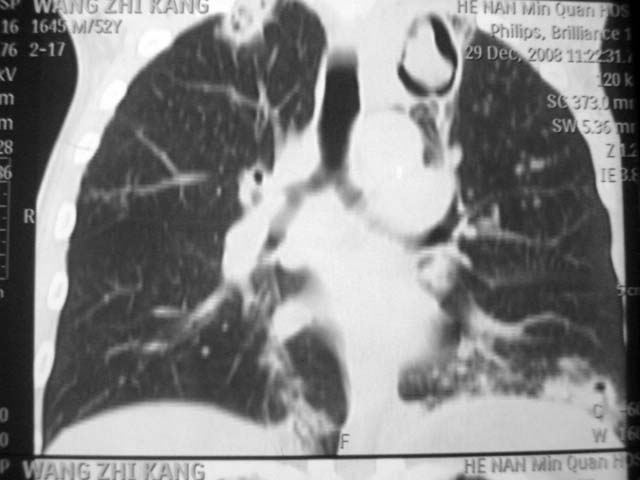

标题: CT17875:肺曲霉菌病?结核?

男,52岁,发热2月,糖尿病史。

抗结核治疗irpz方案,血糖未治疗,空腹15.9左右。症状无好转,左胸痛。

复查ct

结果:两肺继发性肺结核并曲霉菌感染。